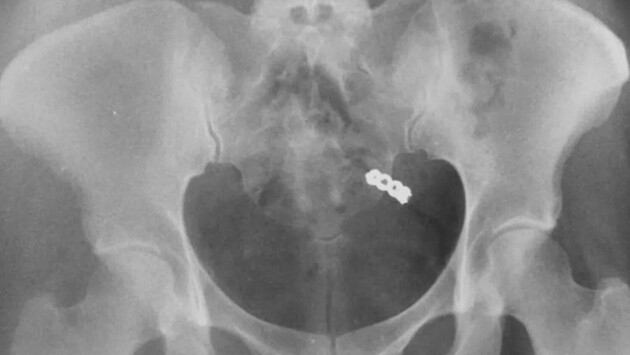

После тщательных поисков в гостиничном номере, Данна решила сделать рентген. Снимок показал, что кольцо действительно было внутри женщины. Врачи заверили ее, что переживать не нужно — украшение выйдет их организма естественным образом, что и произошло на следующий день.